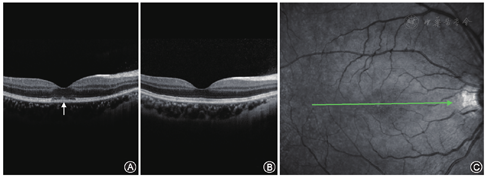

患者女性,20岁。因右眼视力下降,于2013年12月6日就诊于河南省南阳市眼科医院。眼部检查:视力右眼为0.6(-3.50 DS),左眼为1.0(-3.50 DS);双眼屈光间质清晰;眼底检查除右眼黄斑区中心凹反光稍暗外,其余正常。视野及电生理检查均无异常。OCT检查结果见精粹图片1。诊断:右眼黄斑中心凹椭圆体带节段性缺失。经全身应用神经支持剂、维生素及改善微循环药物治疗,于2014年1月13日复诊。患者自觉症状消失,右眼矫正视力为1.0,OCT检查结果见精粹图片1。

右眼黄斑中心凹椭圆体带节段性缺失患者相干光断层成像术检查图像A示右眼黄斑中心凹处色素上皮前椭圆体带节段性缺失(箭头);B示右眼黄斑区缺失的椭圆体带已恢复正常;C示右眼相干光断层成像术在眼底的扫描位置和方向(箭头)